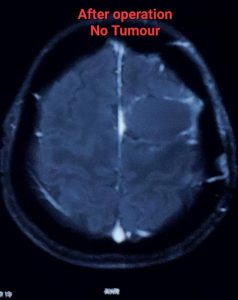

লো-গ্রেড গ্লিওমা সার্জারির পর prognosis বেশ ভালো হতে পারে, বিশেষ করে যদি টিউমার সম্পূর্ণ বা বেশিরভাগ অংশ অপসারণ করা যায়। গবেষণায় দেখা গেছে, দ্রুত এবং কার্যকরী সার্জারি জীবনকাল বাড়াতে এবং খিঁচুনি নিয়ন্ত্রণে আনতে সাহায্য করে। যদিও লো-গ্রেড গ্লিওমা সাধারণত ধীর গতিতে বৃদ্ধি পায়, তবুও এটি সময়ের সাথে সাথে উচ্চ-গ্রেডে পরিবর্তিত হতে পারে। তাই নিয়মিত ফলো-আপ এবং প্রয়োজনে অন্যান্য চিকিৎসা,যেমন – রেডিয়েশন থেরাপি বা কেমোথেরাপি, অত্যন্ত গুরুত্বপূর্ণ।